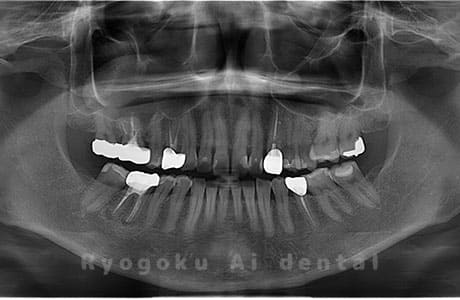

Case04

- 原因

- 上顎の親知らず、下顎の水平埋伏の親知らず

- 治療内容

- 上顎の親知らず、下顎の水平埋伏の親知らずを抜歯したケースです。

<リスク・副作用>

手術後は痛み、腫れ、痺れなどの副作用が生じる場合があります。